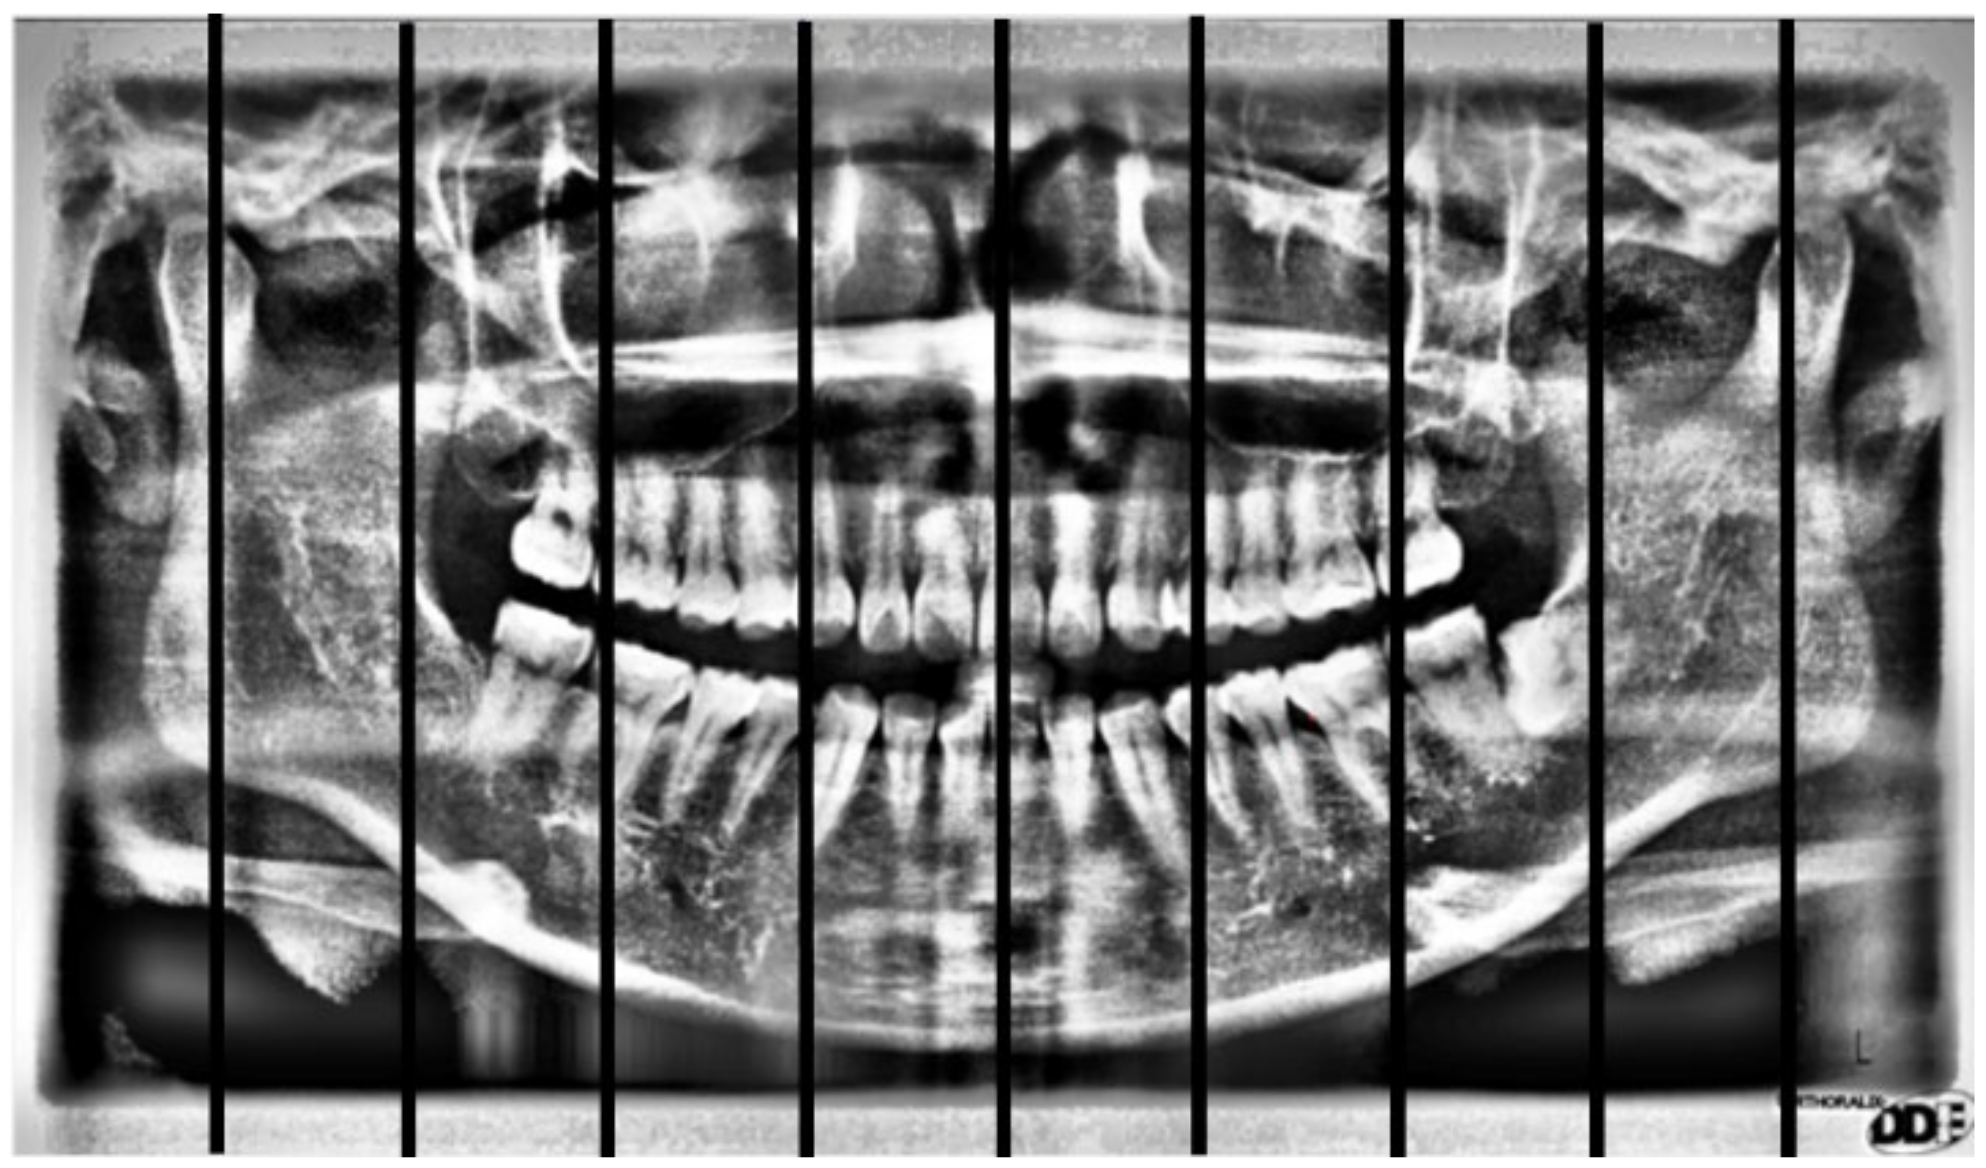

2.2. Image Segmentation

2.2.1. Curve of the Mouth

2.2.2. Curve Adjustment

2.2.3. Positioning Numbers

| Positioning Accuracy Rate | ||

| Method in [26] | Our Method | |

| Positioning accuracy rate | 71.36% | 92.78% |